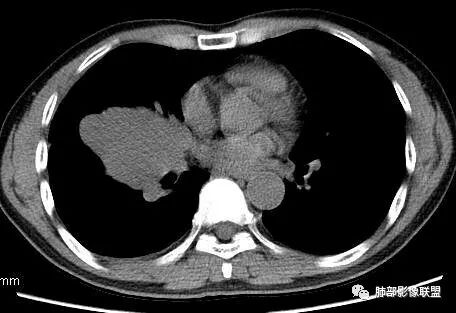

南边:从叶裂的变形,下朝上,越来越朝前扭曲,提示叶裂局部有朝前上推移的趋势

南边:下叶的支气管受压后移、变形

南边:病灶边界清,提示侵袭性弱,膨胀生长为主;这时候我们提示病灶不应该是支气管关系密切,提示间叶来源或胸膜来源

3.肿块常常较大,甚至巨大,病灶边界一般清楚,影像上常有假包膜样结构、有膨胀性生长的特点,影像科医师有时甚至会纠结其来源于肺部或是胸壁纵隔。常见的肺癌肿块,很少有机会能长成这样的规模。

4.边缘可以有浅切迹,部分病灶会有铸型样外观,但大体十分圆钝,不会出现典型的分叶和毛刺,也很少会出现胸膜牵拉。支气管常推移,有明显的支气管阻塞时也较少观察到相关的阻塞性炎症。

5.病灶密度大多不均,不规则坏死液化,少数病例出现钙化。增强扫描常观察到由外而内的厚壁不均匀强化,中央半岛样强化等等,厚壁中或实性区常能显示血管影。一些病灶中央呈现边界清楚囊样变。